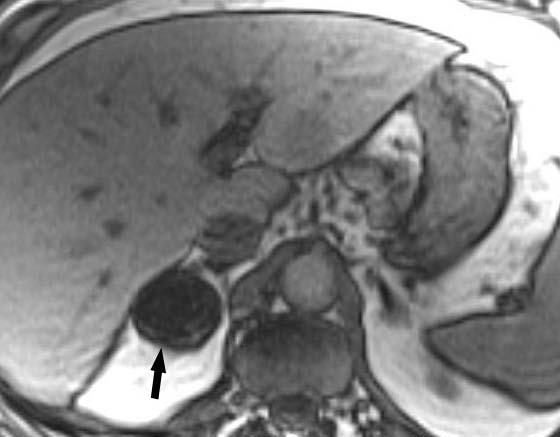

Metástasis hepáticas y suprarrenales

La aparición de nódulos suprarrenales se da en más del 10% de los pacientes con cáncer de pulmón. Dada la elevada frecuencia de adenomas benignos, es crucial la distinción entre éstos y la afectación metastásica. Ésta se puede llevar a cabo con una combinación de estrategias de imagen que incluyen TC, RM y/o PET. Por TC los adenomas suprarrenales típicamente tienen valores de atenuación bajos por la presencia de cúmulos lipídicos. Una lesión suprarrenal con valores de atenuación menores de 10 unidades Hounsfield (UH) en el estudio sin contraste, tiene una probabilidad del 98% de que se trate de una lesión benigna. Dado que ambas lesiones, adenomas y metástasis captan contraste, la valoración rutinaria de la captación no es útil en la diferenciación entre benignidad y malignidad. Si se detecta durante la realización de la TC, realizar cortes tardíos a los 15 minutos de la administración de contraste es importante, ya que si existe un lavado del contraste de más del 50% el diagnóstico de adenoma tiene una sensibilidad del 98% y una especificidad que oscila entre el 92 y el 100%20. La RM con secuencias de desplazamiento químico en la valoración de nódulos suprarrenales tiene una especificidad del 100% para el diagnóstico de adenoma (fig. 14). Sin embargo, la sensibilidad depende de la densidad de la lesión en el estudio con TC, ya que cuanto mayor es la densidad en la TC menos señal perderá en la RM, con lo que resulta más difícil etiquetarlo como adenoma21. La PET presenta una sensibilidad alta en la detección de metástasis suprarrenales, ya que cuando una lesión suprarrenal no muestra signos concluyentes en la TC de benignidad, la ausencia de actividad con la PET hace muy probable dicho diagnóstico. En los casos en que persistan dudas diagnósticas se debe recurrir a la biopsia de la lesión adrenal, especialmente si de este diagnóstico depende el manejo del paciente.

Fig. 14.--Lesión suprarrenal. (A) Tomografía computarizada (TC) abdominal sin contraste que muestra un nódulo suprarrenal derecho de baja atenuación y contornos bien definidos (flecha). (B) Con contraste se aprecia captación del mismo. (C) Resonancia magnética (RM) en fase en la que se identifica el nódulo suprarrenal isointenso con el hígado. (D) En la RM fuera de fase, se pone de manifiesto la pérdida de señal (marcadamente hipointensa con respecto al hígado) característica de estos tumores suprarrenales debido a su contenido lipídico.